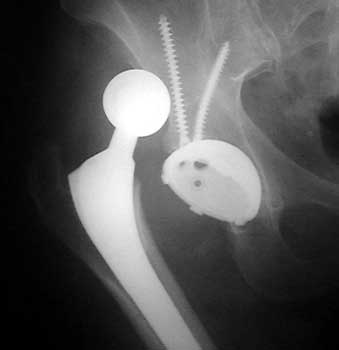

Dislocated femoral component secondary to loose acetabular cup with reverse acetabular inclination